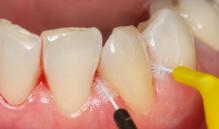

Figure 2.2 : Plaque dentaire accumulée à la base de la canine mandibulaire droite. C’est une zone dans laquelle, on passe souvent trop vite !